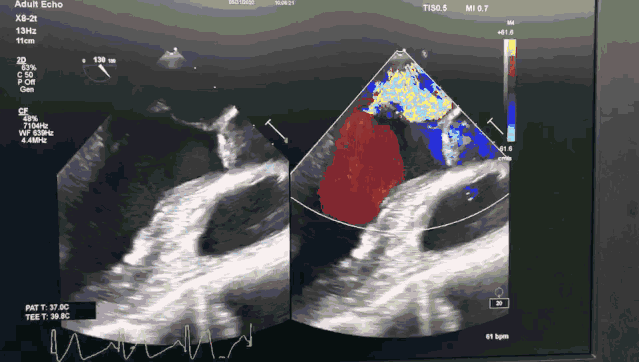

患者是71岁老年男性,体格消瘦,极重度二尖瓣反流,后叶P2及部分P3脱垂,同时合并重度肺动脉高压,STS评分6.1%,外科手术风险高。

今日手术转播的导管操作时间仅用8分钟,一次性成功。患者术后即刻效果满意,二尖瓣反流从极重度减少到轻中度,未出现二尖瓣狭窄,肺动脉高压从重度降为正常,手术效果良好。

图1 ValveClamp术前经食道心超